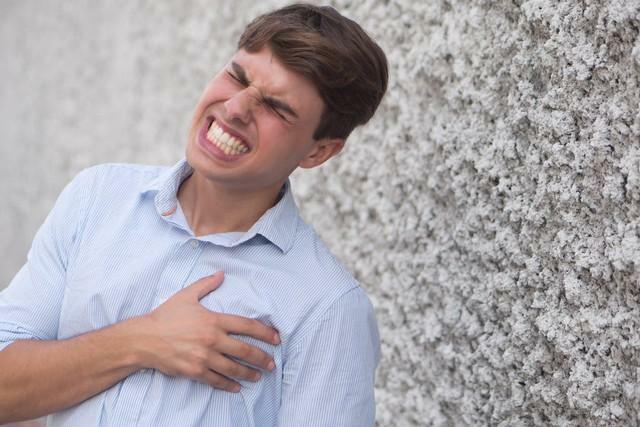

(一)身體痛苦:食道癌患者常常面臨劇烈的胸痛、吞咽困難和胃食管反流等症狀。這些症狀不僅給患者帶來身體上的痛苦,還嚴重影響了他們的飲食攝入和營養吸收,導致體重下降、體力減退和全身虛弱。下面將詳細探討食道癌患者常見的症狀,並解釋其對營養健康的影響。

1.劇烈的胸痛

食道癌患者常常經歷劇烈的胸痛,這是由於腫瘤阻塞了食道通道,導致食物無法順利通過。這種疼痛可以延伸到背部和肩膀,給患者帶來持續不斷的不適感。胸痛使得患者對進食感到恐懼,導致他們減少食物的攝入量和頻率。長期以往,這會導致營養不良和體重下降。